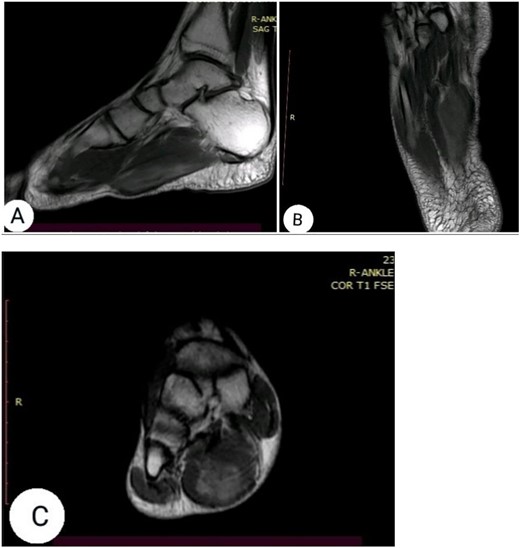

The clinical examination revealed flexion contracture of the third digit of the right foot with dislocation of the proximal interphalangeal (PIP) joint, limited passive and active extension of the second and fourth digits and the presence of little thickness in the skin over the dorsal aspect of the first metatarsophalangeal joint of the foot (Fig. 1). By palpation, there is a non-tender pseudotumor within the plantar aspect of the right foot, without any scare over it (Fig. 2). The X-ray radiographs show inferior dislocation of the PIP joint of the third digit, without any signs of bone lesions or previous fracture (Fig. 3). Ultrasound echomyography shows a significant and heterogeneous increase in the size of the Flexor Digitorum Brevis muscle of the foot. Magnetic resonance imaging (MRI) before gadolinium injuction (Fig. 4) and after gadolinium injuction (Fig. 5) shows a heterogeneous hyperenhancement with irregular margins within the Flexor Digitorum Brevis muscle.

(A) sagittal T2-weighted, (B) sagittal T1-weighted, (C) axial T1-weighted and (D) Short T1 inversion recovery Magnetic Resonance Imaging (STIR) MRI before gadolinium injection.

(A) sagittal T1-weghited, (B) axial T1-weighted and (C) coronal T1-weighted MRI following gadolinium injection showing hyperenhancement within the muscle tissue.